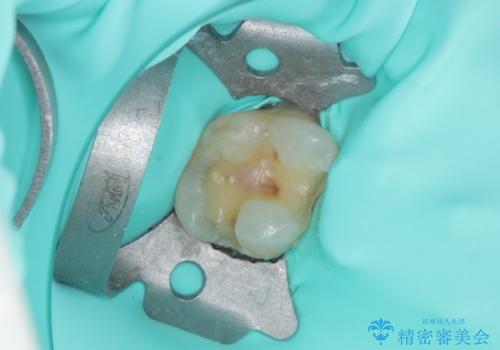

インレーを装着するときは、唾液や血液による接着力の低下を避けるためにラバーダム防湿を行いました。